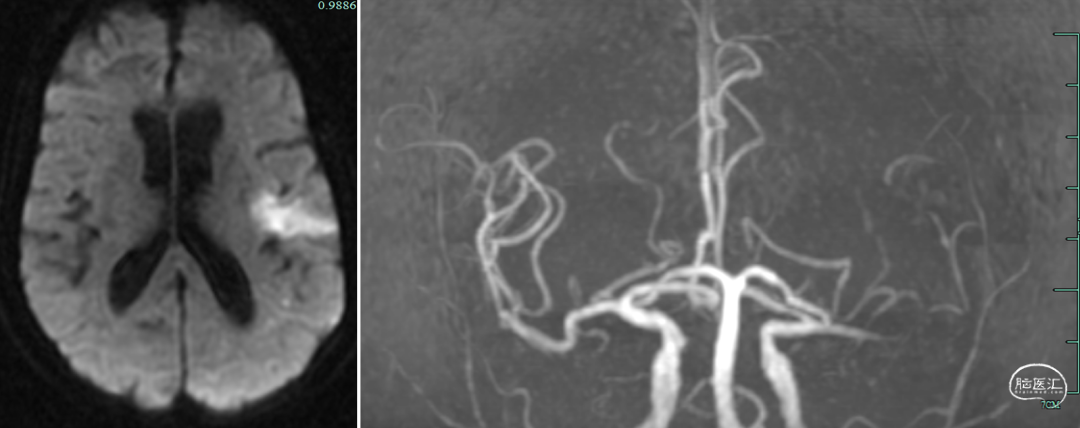

患者老年女性,既往心房颤动病史。因“言语障碍及右侧肢体乏力29小时”入院。患者有明确的大血管闭塞,入院后患者症状加重,MRA提示左侧大脑中动脉闭塞,考虑进展性卒中,患者急诊CTP评估后考虑缺血半暗带大有血管内治疗指征,排除禁忌,拟急诊手术治疗。

患者急性起病,最初起病NIHSS评分3分,最初头颅MRA可见LM1大血管闭塞,但仍有血管残端,结合DWI图像,考虑血栓在分叉部未完全堵塞血管;但后来患者突然加重,考虑侧枝衰竭或血栓位移或二次心源性栓塞可能性大(有房颤病史),计划首先ADAPT抽吸,再Solumbra技术抽拉结合取栓治疗,视情况必要时补充技术。

术后复查头颅CT:无明显出血等表现。